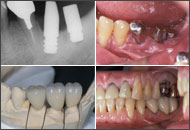

| 審美性考慮前後の比較 |

(7年前頃から審美性を工夫)![]() 右上1は考慮前のもので8Y後、左上1は考慮後のもので6Y 10M後。2005/12/16 |

私は1ピースAQBを植立して17年以上になる。最初の10年近くは口腔清掃性重視で、冠のマージンは歯肉縁ギリギリであった。そのため冠装着後、周囲粘膜が引き締まってくるとチタンの頸部が露出して審美性は劣っていた。当時は口腔清掃性重視からチタンの露出はインプラント補綴の証でもあった。その後インプラントの臨床成績の飛躍的向上にともなって、機能性のみならず審美性も要求されるようになってきた。私もここ7、8年審美性に配慮するようになって、本稿のような工夫で補綴するようになっている。それゆえ1ピースの審美性については、7、8年の予後観察結果で本稿を論じているわけで恐縮の至りではあるが、今後の5年、10年後をさらに経過観察して行きたい。